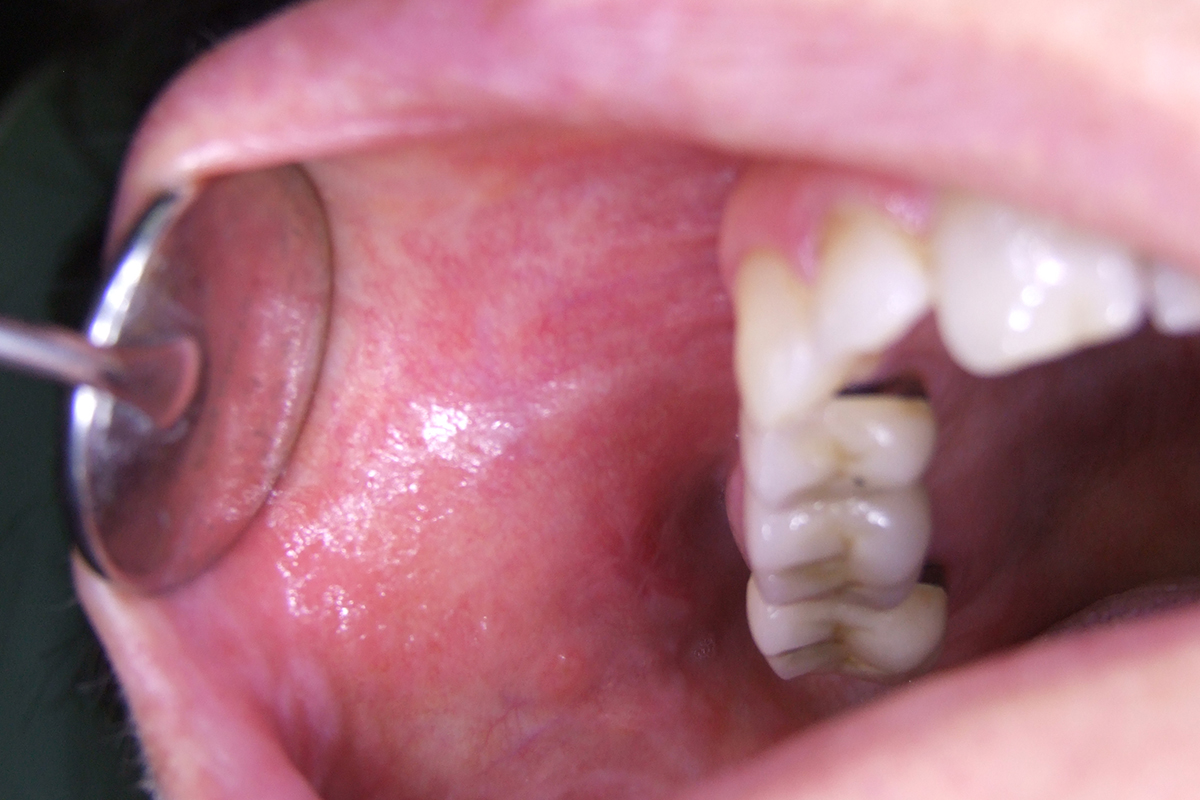

TRAITEMENT DE L’APHTE BUCCAL

L’aphte est une lésion ronde, blanche ou grisâtre, entourée d’un halo rougeâtre, dont la taille peut varier de un à dix millimètres. Le traitement au laser permet de réduire considérablement l’inflammation et la douleur, ce qui accélère le processus de guérison, qui intervient au bout de 2 à 4 jours.